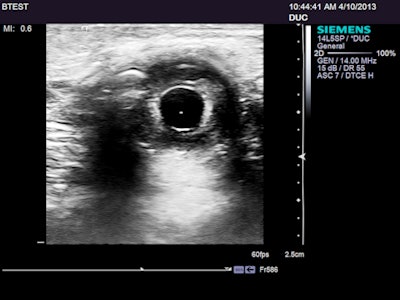

I was really intrigued by one new feature on the S3000 that was billed as a way of cleaning up images. Called Clarify, this seems to be a form of power Doppler that displays flow as black, subtracting intravascular movement from the image -- a kind of blacklight viewing. In any case, this has potential for exposing small peripheral vessels without the color blooming that often wipes out detail in energy and power Doppler usage, especially when filters are set for maximal sensitivity.